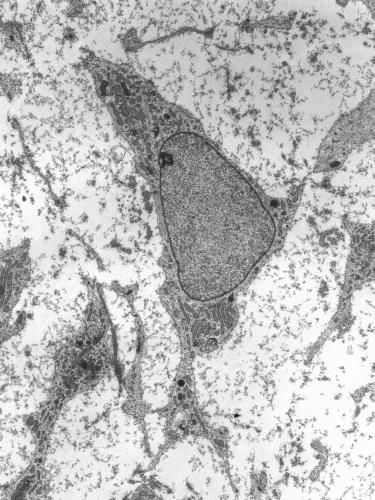

1.3 Эмбриональные и соматические стволовые клетки

Один из основных источников получения стволовых клеток в настоящее время — эмбриональные ткани. Подавляющее большинство публикаций последнего времени посвящено именно эмбриональным стволовым клеткам как наиболее многообещающим для развития клеточных технологий. Отличительными особенностями эмбриональных стволовых клеток являются их способность к бесконечной пролиферации симметричным делением в лабораторной культуре и выраженная клоногенность, то есть способность к образованию из одной первоначальной стволовой клетки целой линии генетически идентичных ей.